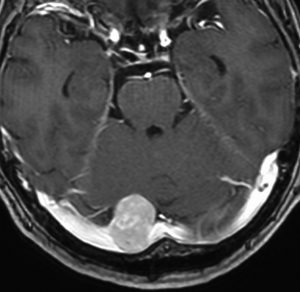

典型的な髄膜腫

この髄膜腫は中程度の大きさのものです。円蓋部髄膜種という最も多い最も手術の簡単なタイプです。麻痺や失語症やてんかんなどの症状はありません。とても美しくて若い女性の髄膜腫でしたが,子供に遺伝はしませんし,癌などと違ってタバコなどこれといった原因がなくて発生するものです。

MRIでの髄膜腫の見え方は撮影の仕方によっていろいろです。左からT1強調画像,T2強調画像,フレア画像といいます。腫瘍の横に小さく白い領域がありますが,これは脳の腫れた部分で脳浮腫といいます。髄膜腫があると周囲に脳浮腫が生じることがあります。

最も見やすいのが,ガドリニウム造影剤を注射して撮影するものです。一般的に髄膜腫は造影剤で白く映し出されます。この腫瘍は左脳側にあります。MRIの軸面という輪切りの写真では左右が逆になりますから注意してください。脳を下から見た図になっています。MRIはいろいろな方向から腫瘍を見ることができますが,右は冠状断という正面から見た図です。よく見ると腫瘍の上と下のはじっこに線状に糸を引いたように造影される部分があります。これをテールサイン(しっぽのサイン)といいます。腫瘍が硬膜に沿って延びている可能性があることを示しています。